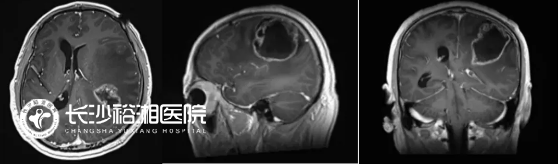

(術(shù)前:頭部增強(qiáng)MRI:左側(cè)額頂葉巨大占位,伴瘤中央壞死,周圍大片水腫,占位效應(yīng)明顯)